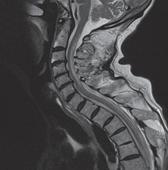

使機體處于應激狀態的創傷有:嚴重外傷、大面積燒傷、顱內疾病、腦外傷、腹部手術等。